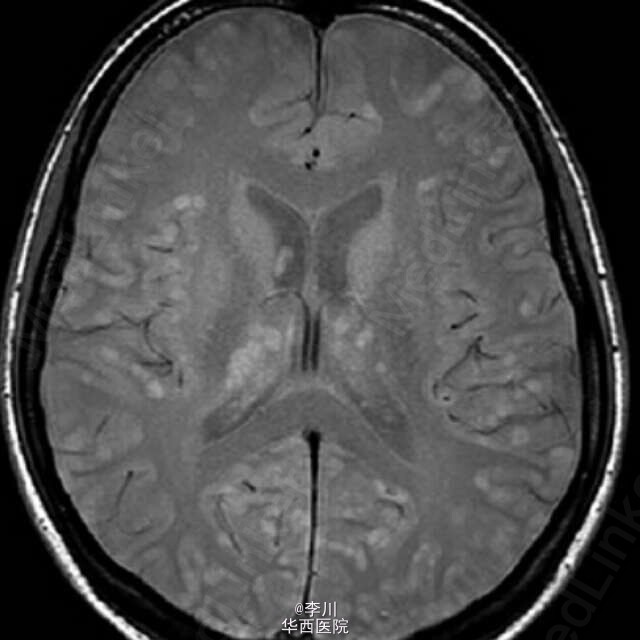

患者女性,38 岁,肺腺癌,年吸烟量 15 包。胸部 CT 表现右上肺脊柱旁肿物。胸膜活检病理证实为乳头状肺腺癌。头颅磁共振显示除灰质外,大脑皮质,基地核和丘脑 粟粒状结节。可以媲美粟粒性肺结核Dziadziuszko K, Szurowska E, Pienkowska J, et al. Miliary Brain Metastases in a Patient with ROS1-Rearranged Lung Adenocarcinoma: A Case Report[J]. Journal of Thoracic Oncology, 2014, 9(5): e34-e36.